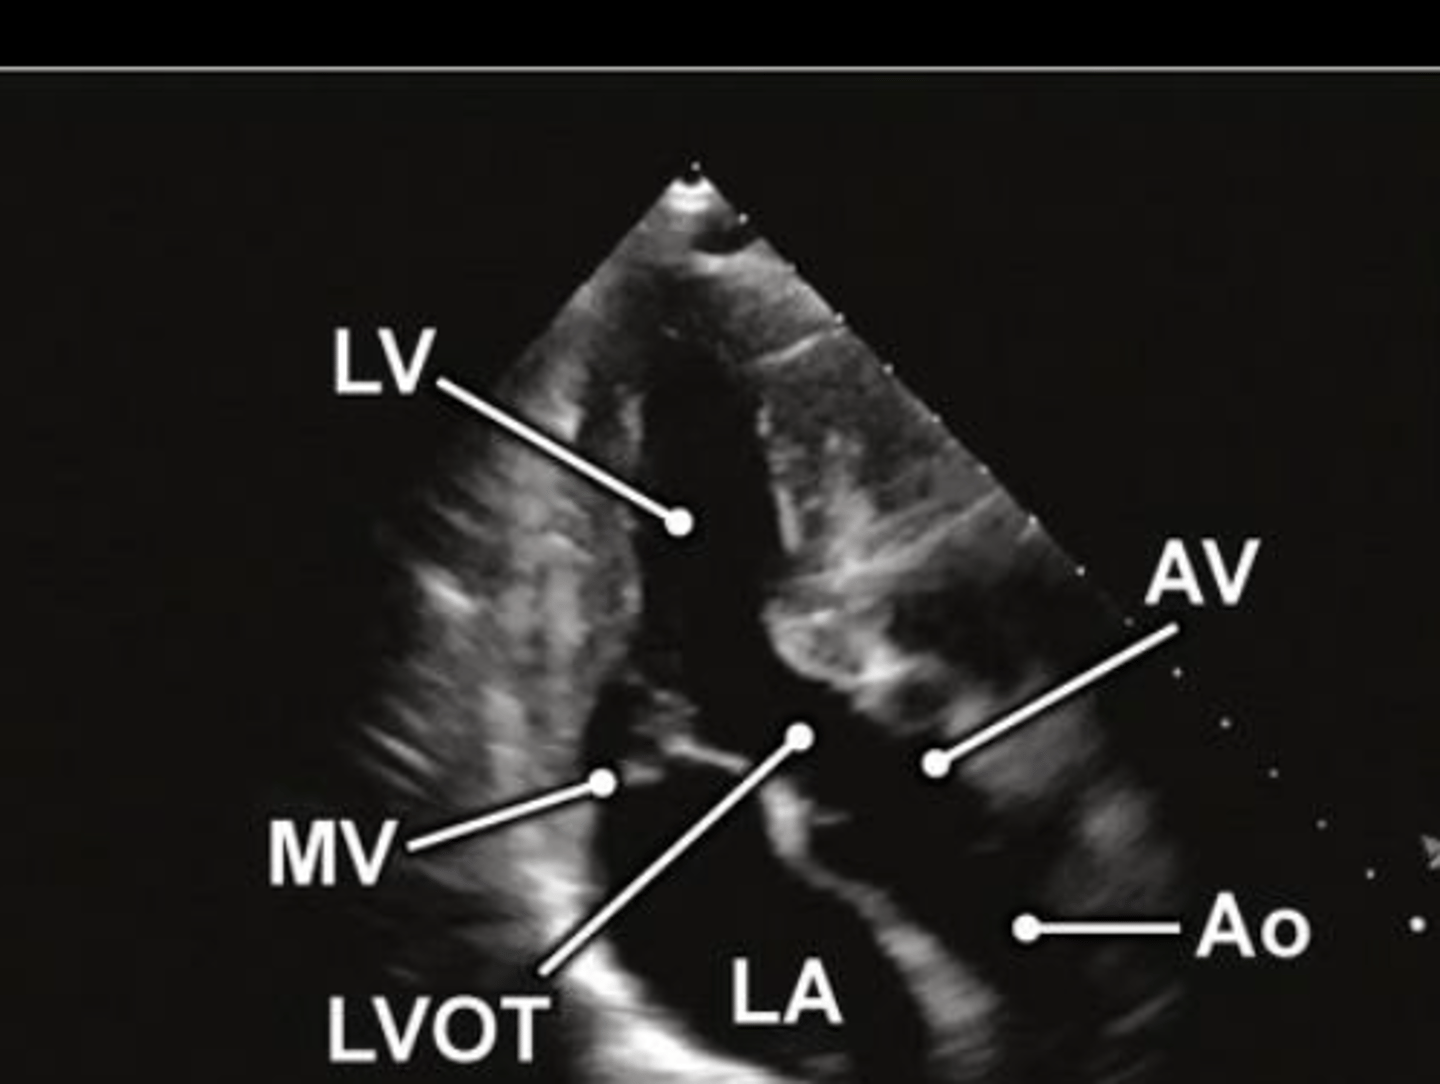

A3 is used to visualize ___ and ____

MV and AoV